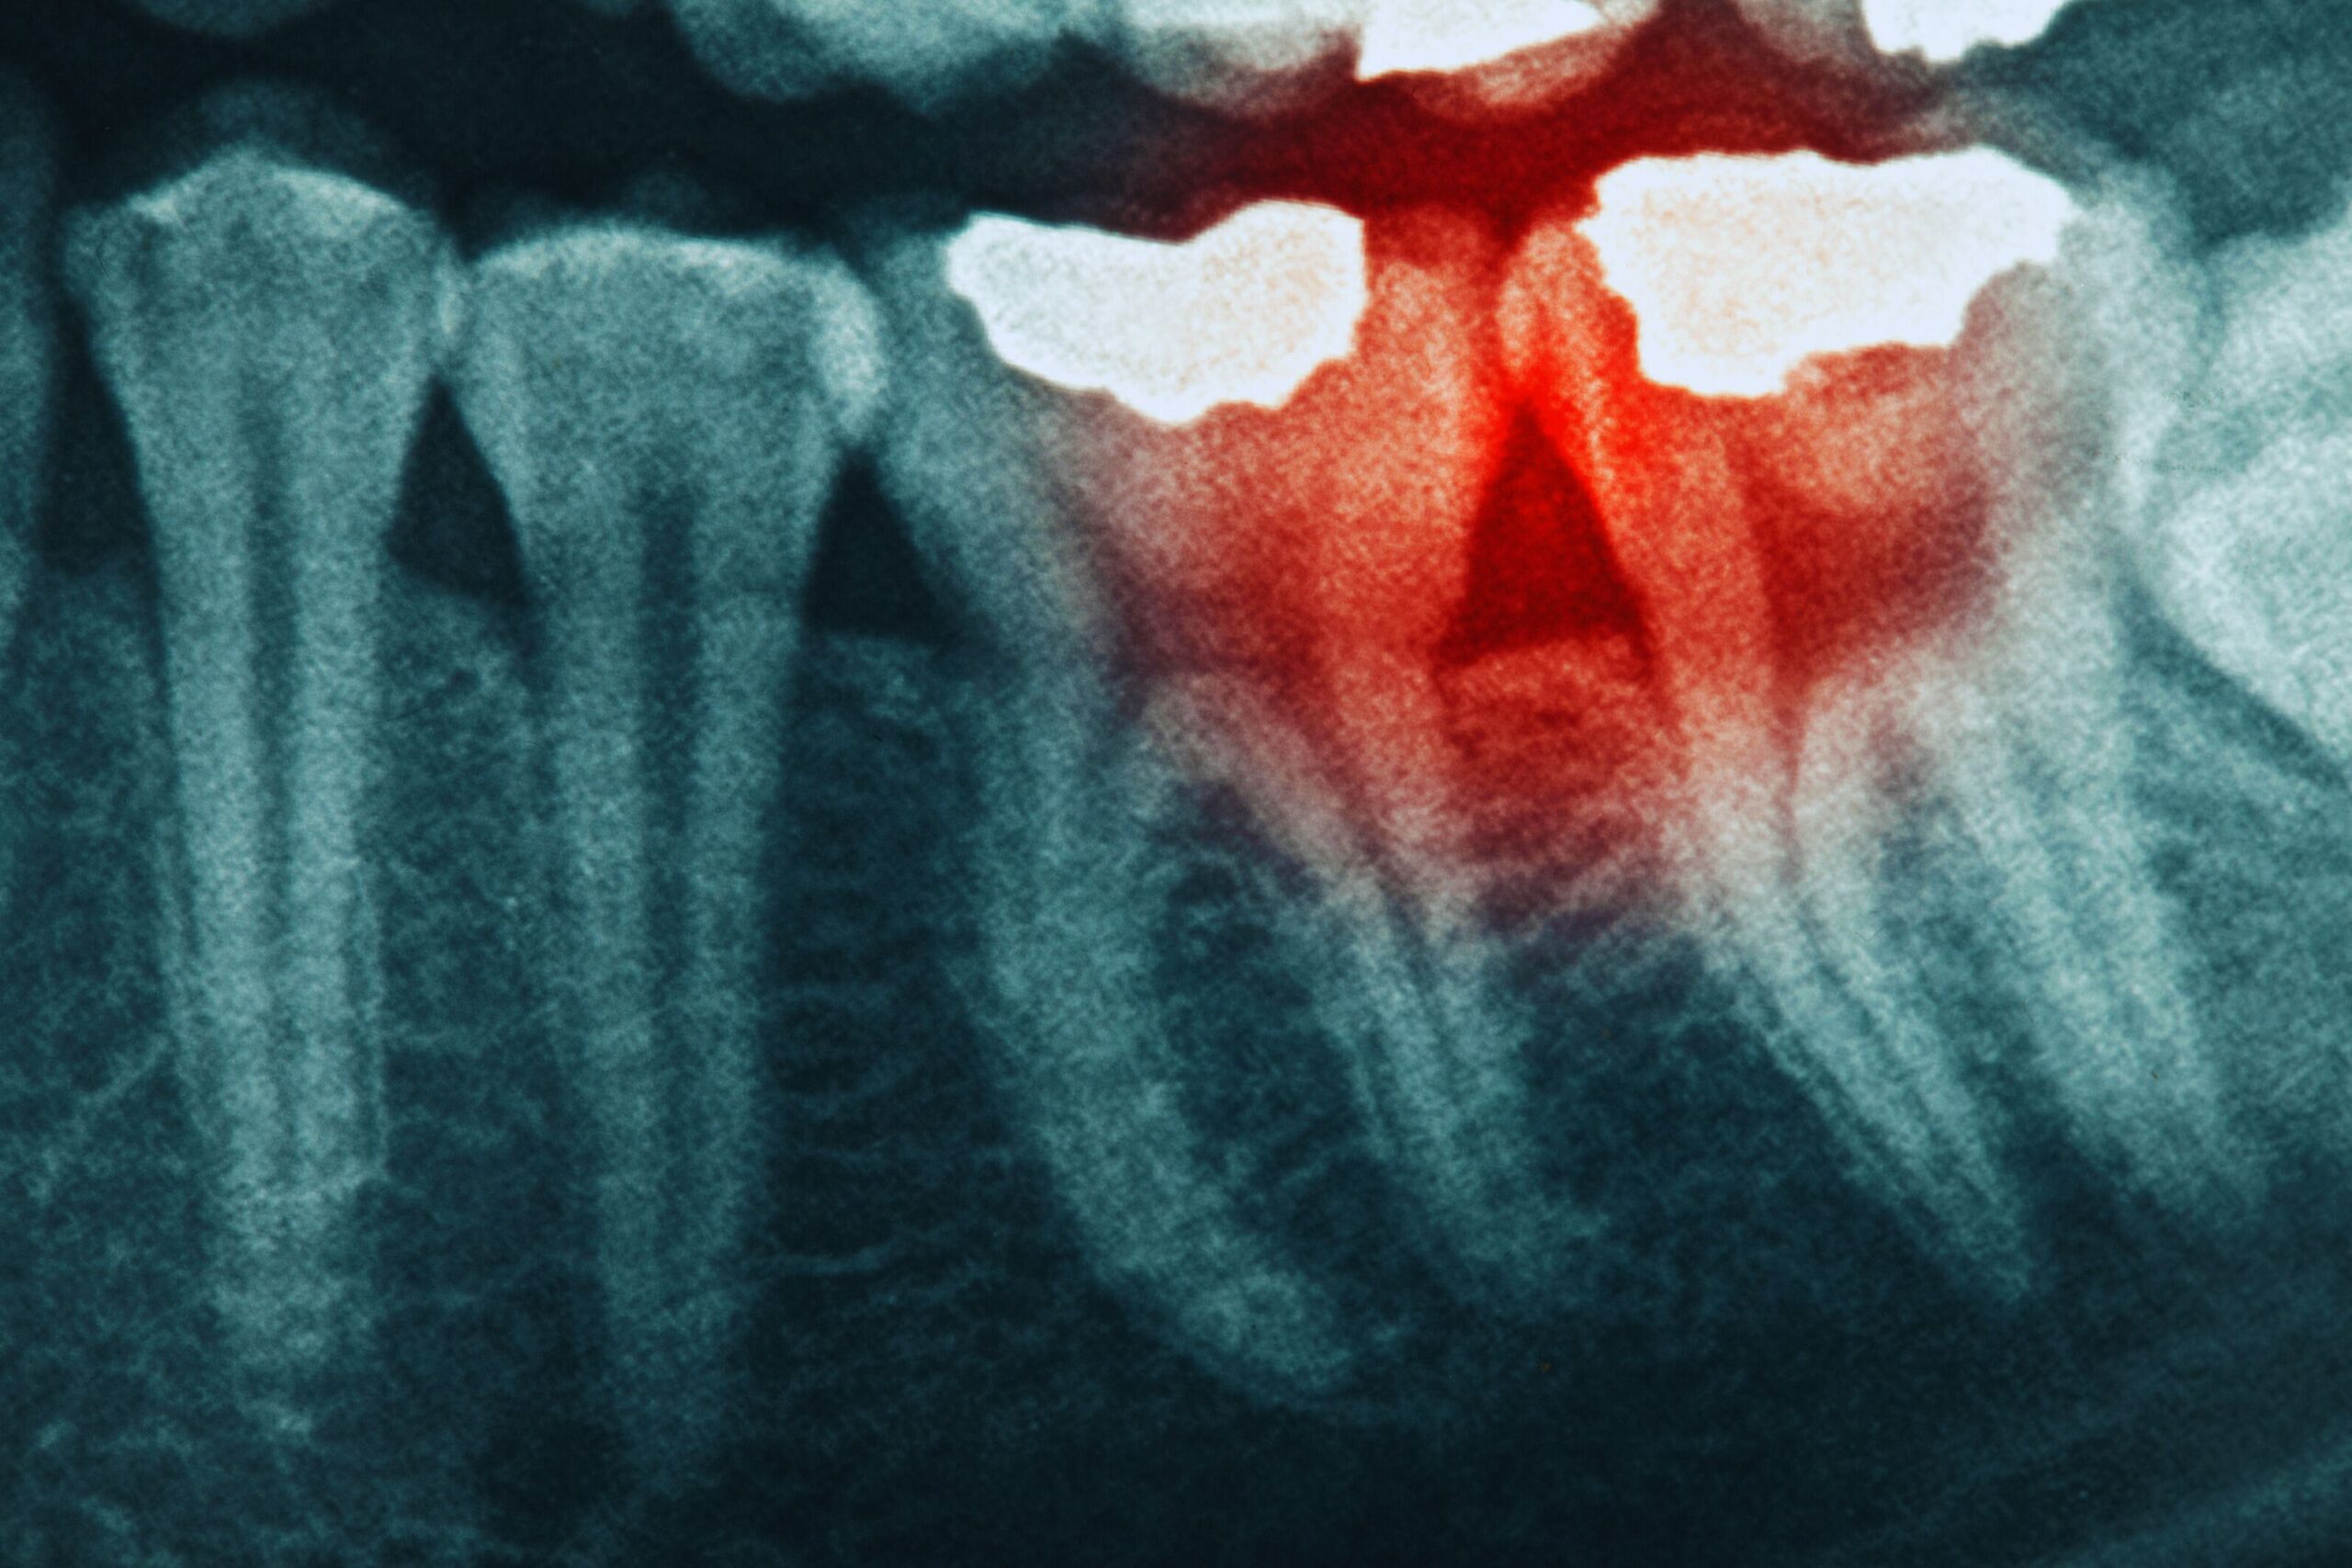

Periapical images focus on one tooth at a time and include the full root. They help us evaluate the health of the root and surrounding bone, detect abscesses, and identify infections that may involve the nerve of the tooth.

Can x rays show periodontal disease

X rays are a powerful tool, but they are not used alone. Periodontal disease is diagnosed by combining imaging with a clinical exam. To confirm periodontal disease, we evaluate bone levels on x rays, then compare those findings with gum measurements and signs such as bleeding.

Bone loss seen on an image may sometimes reflect past disease that is currently stable. That is why the clinical exam matters. When we combine x rays with gum measurements, we can determine whether disease is active, whether it is stable, and what type of care is needed.